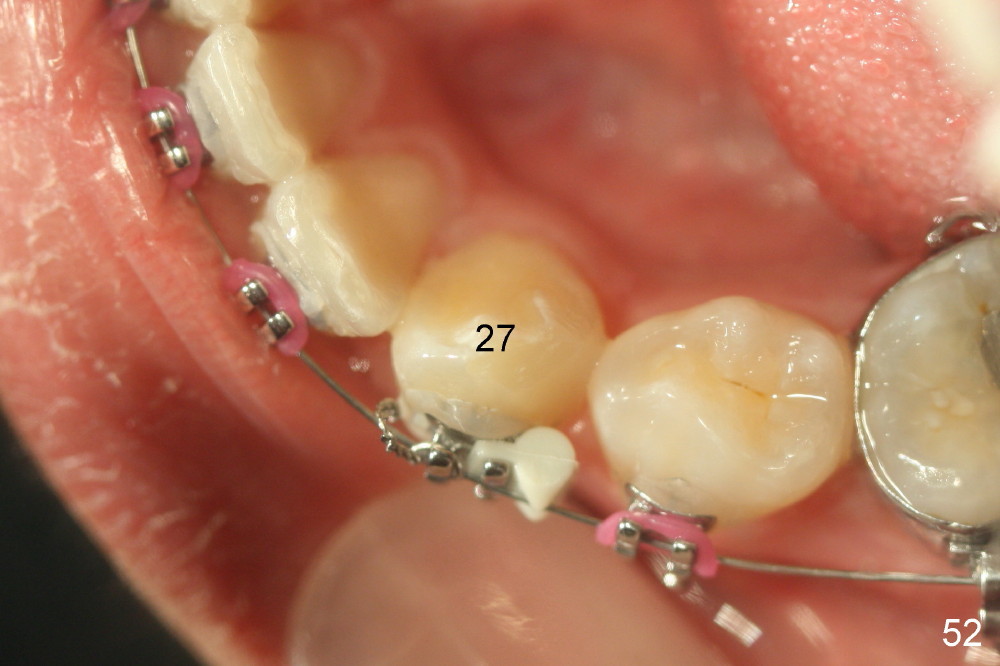

Two months later, LL7 (#18 in Fig.53,54) appears to be uprighted by itself (probably due to mesialization of the teeth mesial to it); a bracket is placed with .012 niti wire. No power chains are used to close the diastemata among the upper teeth, since the anterior overjet is minimal. A rotation wedge is placed in the distal wings of #27 to fix rotation. Is it right?